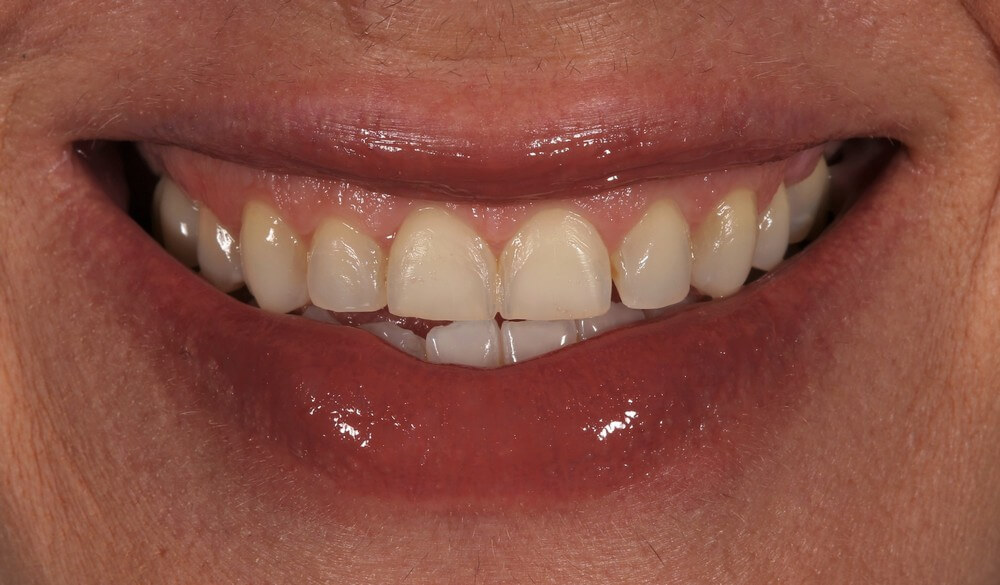

Πριν